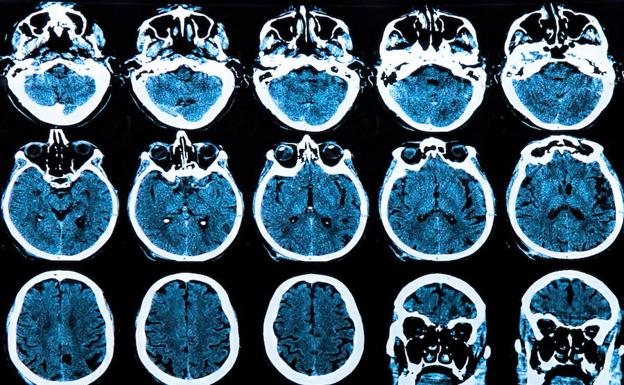

Investigadores de la Universidad de California (UC) San Francisco, en Estados Unidos, han descubierto cómo una mutación en un regulador genético llamado promotor TERT -la tercera mutación más común entre todos los cánceres humanos y la mutación más común en el glioblastoma mortal del cáncer cerebral- confiere 'inmortalidad' a las células tumorales, lo que permite la división celular no controlada que impulsa su crecimiento agresivo.

La investigación, publicada este lunes en 'Cancer Cell', encontró que las células de glioblastoma derivadas de pacientes con mutaciones del promotor TERT dependen de una forma particular de una proteína llamada GABP para su supervivencia. GABP es fundamental para el funcionamiento de la mayoría de las células, pero los investigadores descubrieron que el componente específico de esta proteína que activa los promotores de TERT mutados, una subunidad llamada GABP-1L, parece ser prescindible en las células normales.

Además, descubrieron que eliminar esta subunidad usando la edición genética CRISPR ralentizó drásticamente el crecimiento de las células cancerosas humanas en los platos de laboratorio y cuando se trasplantaron en ratones, pero la eliminación de GABP-1L de las células sanas no tuvo un efecto discernible. «Estos hallazgos sugieren que la subunidad *1L es un nuevo fármaco objetivo prometedor para el glioblastoma agresivo y potencialmente para muchos otros cánceres con mutaciones del promotor TERT», afirma el autor principal del estudio, Joseph Costello, un destacado investigador de neurooncología de UCSF.